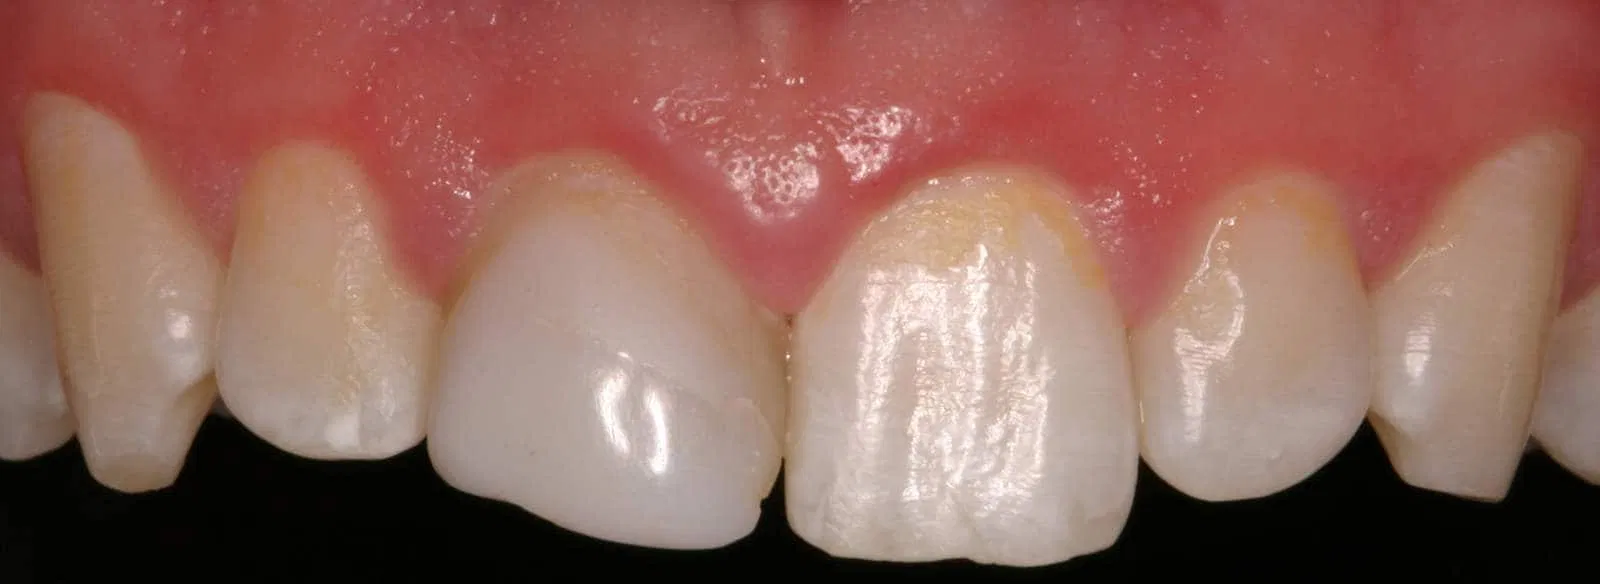

Ceramic Post/Core; Ceramic Crown-Bonded

After: Followed by delivery of a custom ceramic post/core foundation, and a bonded all-ceramic full coverage single restoration (crown).